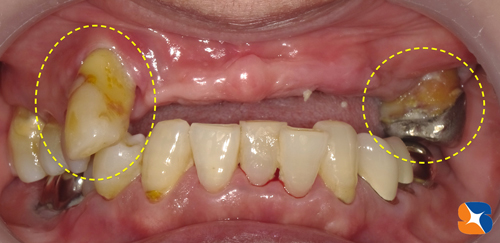

寝屋川市から40代の女性。主訴は「入れ歯で苦労している。医療従事者でしゃべる仕事をしている。上顎の骨が薄くて浅いのでインプラントは難しいと言われ続けてきた。先生の御意見をお聞かせ下さい。」

CTを使って骨の状態(骨の厚みと高さ)をチェックすると、厚みも高さもかなり不足していましたので、インプラント治療をするのなら人工的に骨を増強する必要がありました。また、黄色の点線の歯は、乳歯のようにグラグラしているので、抜歯をして当日その痕にインプラントを移植することもお伝えしました。

この画像は、ほお骨の横から人工骨を入れた所に、インプラントを植立したところです。

約4時間に及ぶ施術が終わりました。

〈内容〉

•抜歯2本→抜歯痕にインプラントを2本移植

•2㍉幅のほお骨の横から穴を開けて人工骨を増強する手術(サイナンスリフト)

•7連結の仮歯をセットして帰っていただく。

※静脈鎮静法を使って、リラックスした状態で施術を受けてもらっています。

※採血をして再生療法医療(CGF、AFG)を行い、人工骨の安定を図りました。